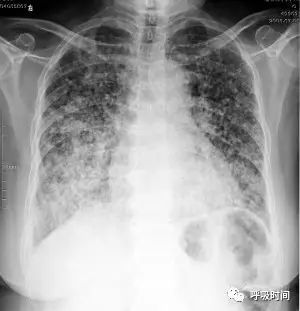

图片

图 13 粟粒结节影——浸润性肺腺癌(细支气管肺泡癌)。双肺弥漫分布的粟粒结节影,特点:大小不一,中下肺野明显